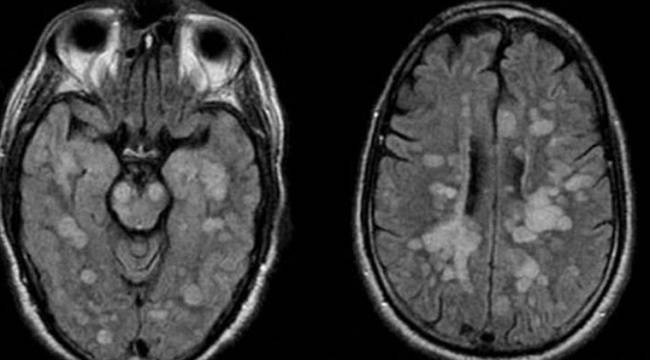

Talihsiz çocuğa vücudun bağışıklık sistemi kendisine saldırarak omurilik ve beynin şişmesine neden olan nadir bir akut yayılmış Ensefalit (ADEM) teşhisi koyuldu.

Braun’un Akut dissemine ensefalomyelit (ADEM) santral sinir sisteminin immun aracılıklı bir bozukluğuna yakalandığı bildirildi.